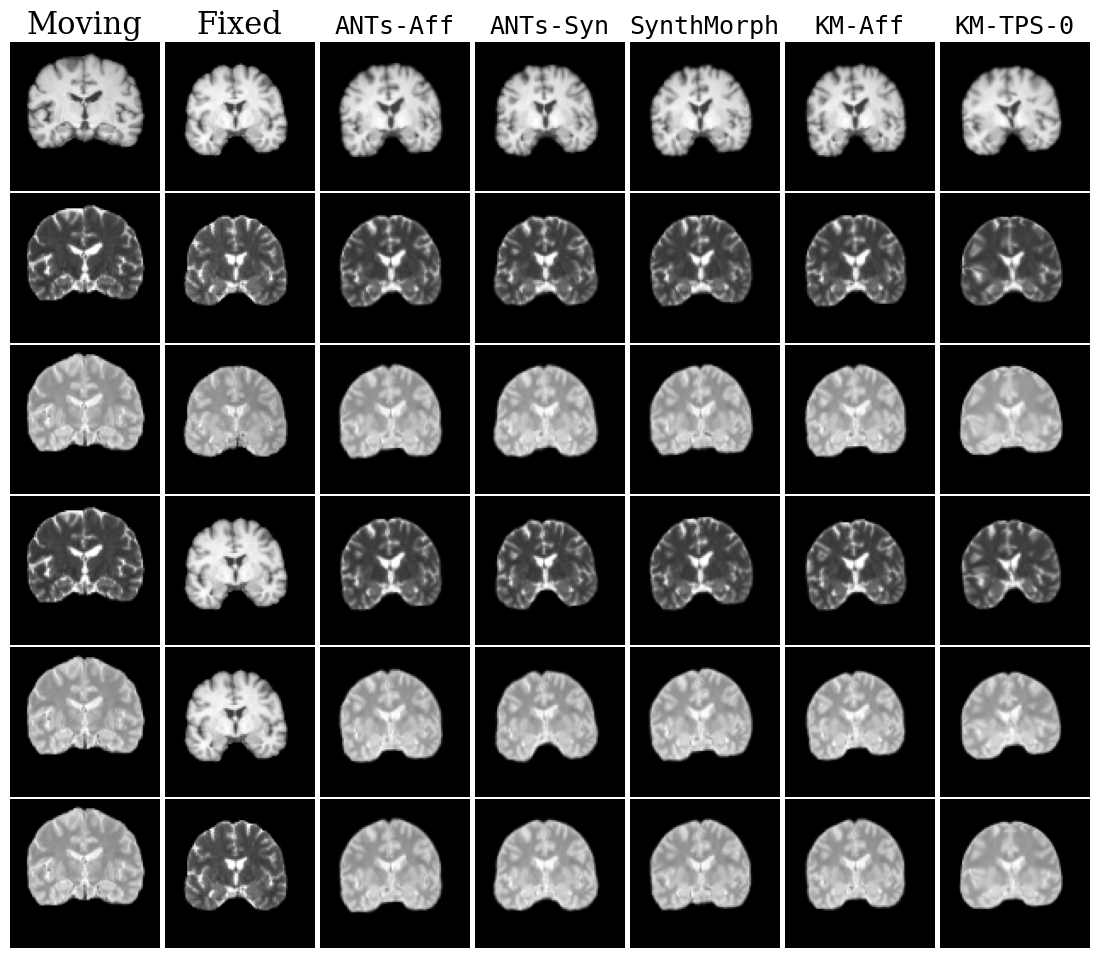

Refer to caption

Fig. 17: Qualitative results for all models. Moving image is not misaligned. DLIR results are omitted to save space.